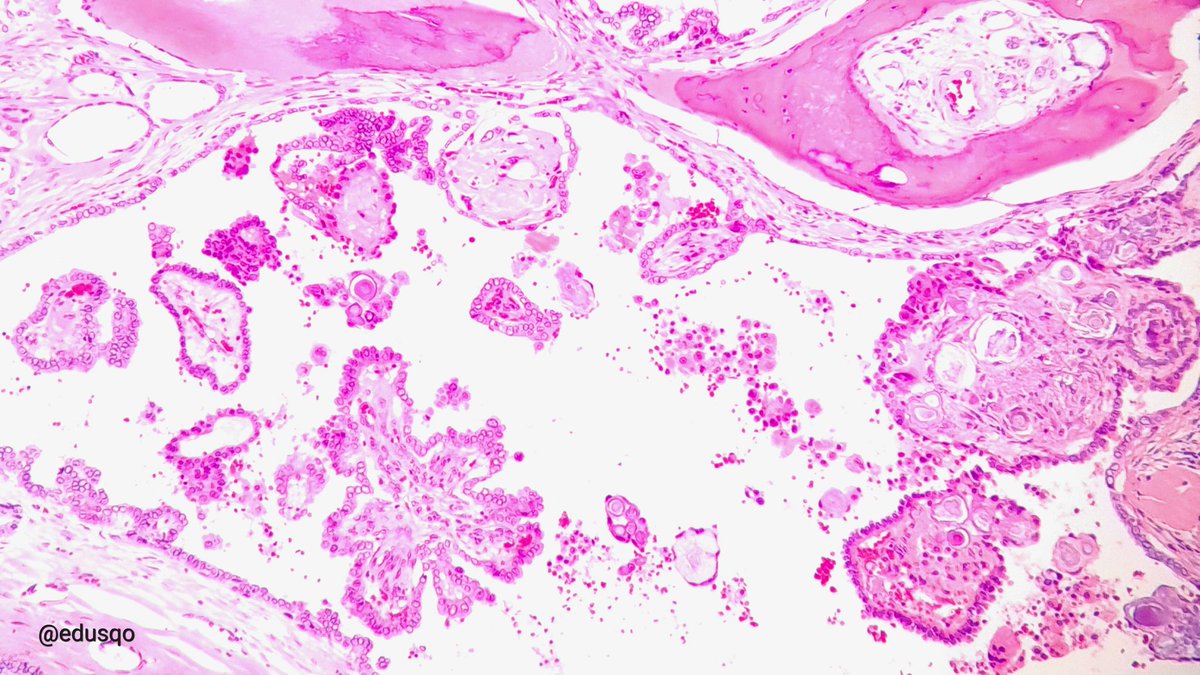

What is this? - easy; Where are we? - difficult? 😃Dr. Luca Olaleke Folaranmi Tania Labiano Aurélien Morini, MD, MSc 🇫🇷🇪🇺💙💛 Celina Stayerman MD 🔻Nusrat Zahra🔻🇵🇸 @miss_me1986 Gonzalo De Toro Tristan Rutland MBBS FRCPA IFCAP GI James Anandi Lobo, MD Angel Panizo MD, PhD 🇪🇸 🔬 Sumanta Das Lorand Kis Laura G. Pastrián MD Carlos Miguel Ruiz Carlos Nieves

benign nodule of the breast😃#breastpath Dr. Luca Olaleke Folaranmi Alexander Damron, MD Liza Quintana, MD Anne Grabenstetter Tania Labiano Jenny Pincus, MD Aurélien Morini, MD, MSc 🇫🇷🇪🇺💙💛 Celina Stayerman MD 🔻Nusrat Zahra🔻🇵🇸 @miss_me1986 Gonzalo De Toro Tristan Rutland MBBS FRCPA IFCAP Sumanta Das Israh Akhtar Khan Lorand Kis Carlos Miguel Ruiz Carlos Nieves